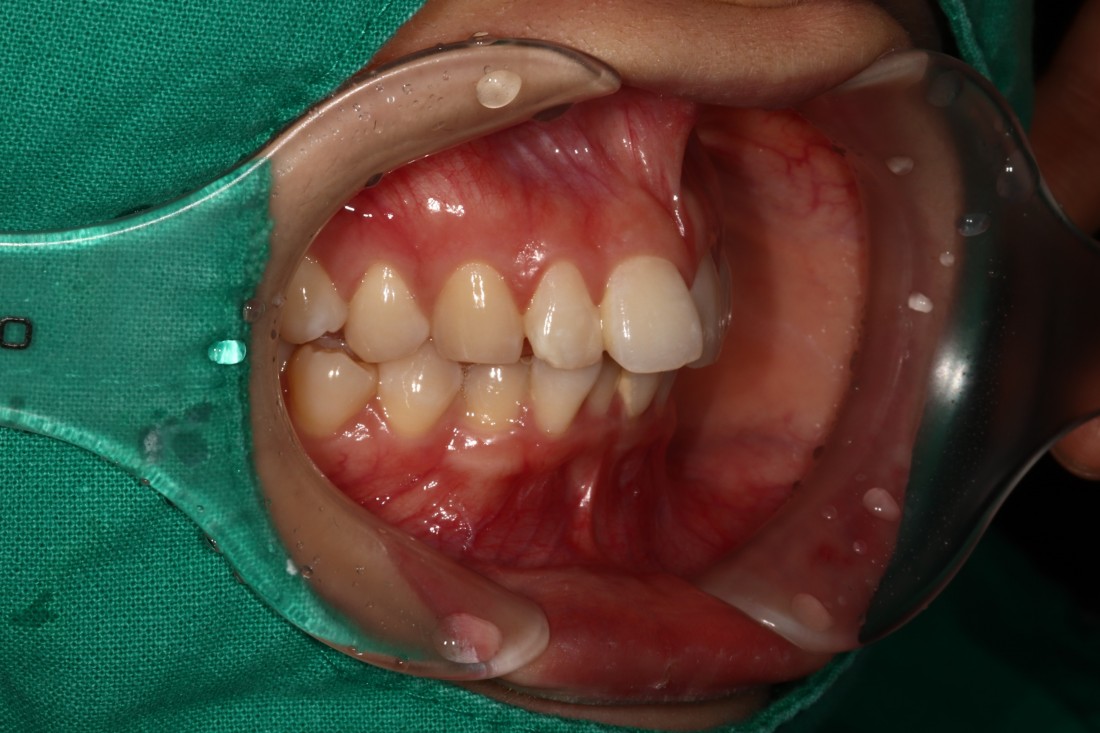

광주 교정치과의 교정전문의 대표원장님은

지난 20년 넘는 기간동안

오직 치아교정 진료만을 담당해오고 계신

실력있는 교정전문의입니다.

지금도 조선대학교 교정진료실의

후배 교수님들이 자주 질문을 해오실 정도로

교정실력면에서 인정을 받고 계신데요.

광주 교정치과 추천하는 이유는

실력을 입증받은 교정전문의 진료로

어떠한 케이스도 잘 대처하여

성공적인 치아교정을 완성할 수 있기 때문입니다.